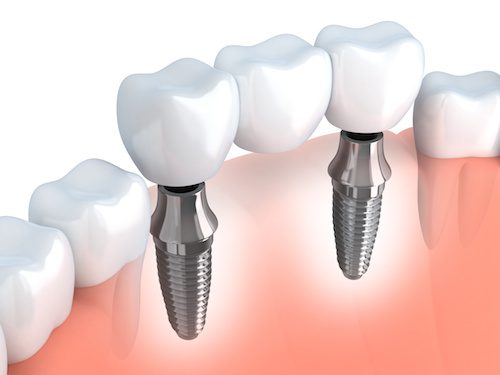

Implants

Although this is not the cheapest tooth replacement option, it is also the very best. Your dentist will insert an artificial “root” into your jawbone. This has to be given some time to settle in. The bone grows around it making it firm and ready to receive your new tooth. Once your new tooth is attached to the implanted root, it’s a permanent fix unless you have some accident.

People prefer implants because it’s a real tooth replacement that looks and feels perfectly natural. But there is another advantage: having the implant in your jaw prevents deterioration of the bone, stimulating it to repair itself.

Finally, if you consider that bridgework or dentures do need maintenance and replacement from time to time, implants can actually cost a lot less than the so-called “cheaper” options over the course of time.